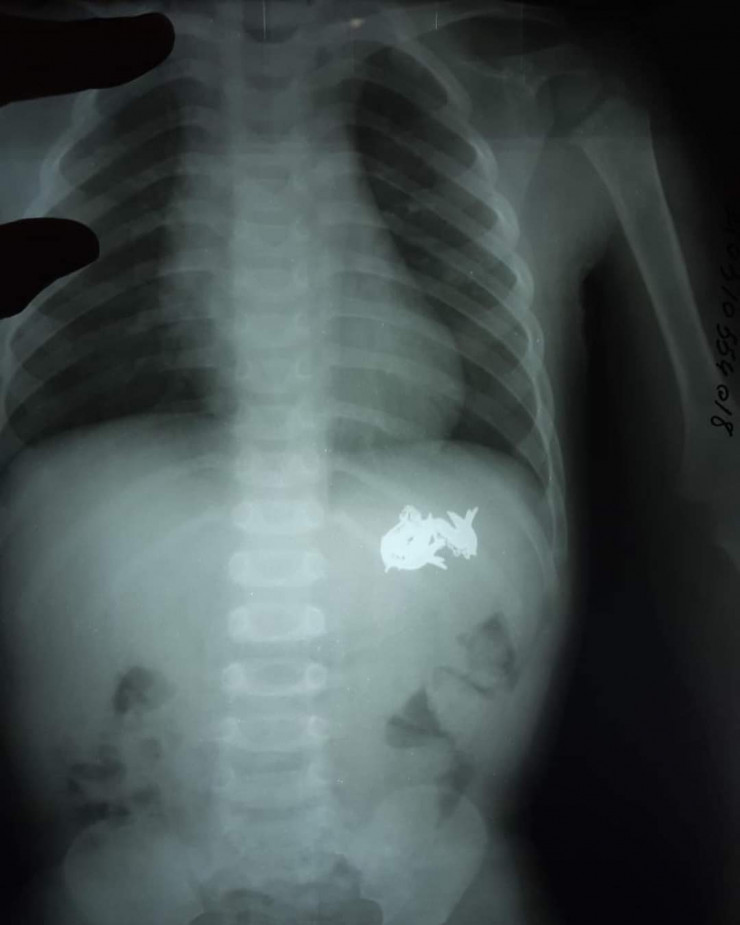

Золотой браслет и сережки извлекли кызылординские врачи из желудка двухлетнего мальчика, передает корреспондент Tengrinews.kz.

"Мы провели обследование ребенка с помощью эндоскопа. У него в желудке были обнаружены инородные тела. Это были украшения из золота. Мы их благополучно извлекли", - рассказал врач хирург-эндоскопист многопрофильной областной детской больницы Серик Нусипхожаев.

Фото предоставлено многопрофильной областной детской больницей